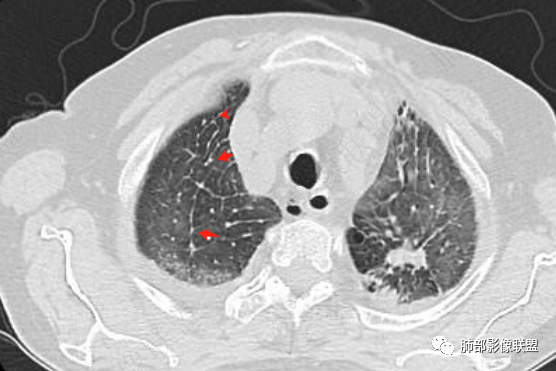

两肺叶后肋膈角区见多发蜂窝状结构破坏表现,双肺叶小叶间隔增厚,左肺上叶后段及舌段和右肺中叶胸膜炎性肉芽肿特点,双侧胸腔少量积液,有类风湿性关节炎治疗史,结缔组织相关性间质性肺病。

发热,有类风湿性关节炎、糖尿病基础病,长期口服激素及免疫抑制剂,双肺多发磨玻璃影及小叶间隔增厚,蜂窝影,支气管扩张考虑非特异性间质性肺炎存在,左肺上叶不规则结节影,周围长毛刺局部肺气肿,考虑慢性炎症,结合pct及crp升高考虑细菌感染,另真菌g升高考虑结合宿主因素,真菌感染需要积极排除。

两下肺多发蜂窝状表现,双肺小叶间隔增厚,双肺磨玻璃影及部分炎性肉芽肿表现,双侧胸腔积液,有类风湿性关节炎治疗史,结缔组织相关性间质性肺病。患者C反应蛋白和降钙素原都高,是否合并细菌感染

老年女性,外阴溃疡伴发热,有类风、糖尿病病史,血象及炎症指标高,G试验升高;影像:磨玻璃密度(中央分布为主)胸膜下蜂窝状改变心影增大、两侧胸腔少量积液;小叶间隔增厚,结节;考虑:1.中央分布为主的GGO需考虑:肺水肿、出血、PJP、肺泡蛋白沉着症;2.胸膜下间质性改变蜂窝肺,需考虑UIP、CTD-ILD,综合:两元论:CTD-ILD奴卡,或肺水肿

①影像表现复杂:较弥漫间质性改变,对称磨玻璃密度为主,小叶间隔增厚,有一定重力分布趋势,未见明显纤维化,气囊及蜂窝位于肺边缘,未见典型“月弓征”。心脏影增大,双侧胸腔积液。

这即可见于间质性肺病,也可见于真菌感染(如PJP)、病毒感染,类风湿,以及肺水肿等等。

上肺斑片影、结节影,夹杂纤维条索影,边界清楚,新旧不等,胸膜牵拉明显等等,符合较典型继发性肺结核表现,但它却未必是此次就医主要责任病原体!